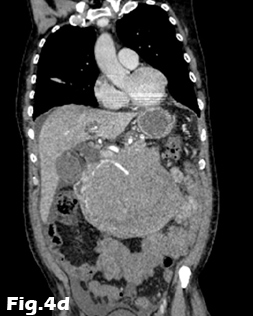

We present the case of a 59-year-old male, previously fit and well who presented to the General Practitioner with a 3 week history of epigastric pain, shortness of breath and unintentional weight loss. On examination, there was evidence of abdominal distension and palpable swelling of left testes. Initial investigation with US of the scrotum revealed dilated (maximally 5.3mm) left pampiniform plexus with retrograde flow on Doppler ultrasound and Valsalva manoeuvre, consistent with an extensive unilateral varicocele (Fig. 1 and 2). Subsequent abdominal ultrasound demonstrated moderate ascites, dilated common bile duct, large right sided pleural effusion and a large 14x14cm solid, vascular epigastric mass. This prompted urgent surgical referral and further cross-sectional imaging (Fig. 3). CT abdomen showed a large soft tissue density retro-peritoneal mass obliterating the portal mesenteric vein circulation and causing the left varicosity (Fig. 4). Ultrasound guided biopsy of the central abdominal mass confirmed a Stage IV Mantle cell Lymphoma.

Figure 4: Contrast-enhanced CT of the abdomen demonstrating the retro-peritoneal mass. Axial images (A, B) of the retro-peritoneal mass encasing the superior mesenteric artery. Sagittal reformatted image (C) of the retroperitoneal mass demonstrating the superior mesenteric artery encasement, the extent of the mass and pleural effusion. Coronal reformatted image (D) of the retroperitoneal mass. Note is made of fluid in the perihepatic space and within the pelvis.